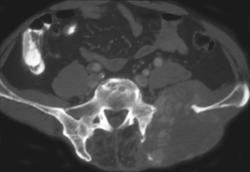

Intramuscular Abscess